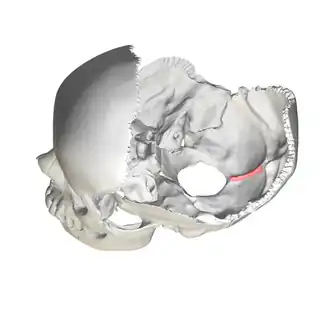

Human skull side view (parietal bones removed). Position of internal occipital crest shown in red. | |

Position of internal occipital crest (shown in red). Animation.

Position of internal occipital crest (shown in red). Animation. -